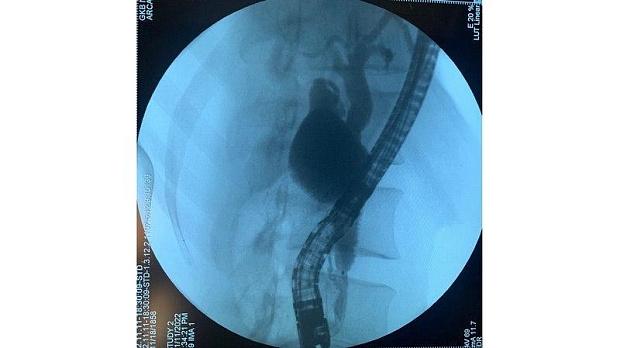

В срочном порядке пациент взят в операционную. В условиях интубационного наркоза в положении пациента на левом боку выполнена дуоденоскопия с последующей холангиографией.

Эндоскопически: Бдс в типичном месте, интрамуральный отдел прослеживается на протяжении 1,5, отечен. Устье сокращается, отмечается поступление желчи с фрагментами чёрной слизи. Канюляция по проводнику катетером (паппилотомом) со второй попытки. При введении контраста, холедох на всём протяжении до 1,2см с неподвижным дефектом наполнения до 2,0 см в интрапанкреатической части. Паппилотомия до границ сфинктера Одди. При ревизии корзиной Дормиа извлечён гельминт до 4,0 см длиной, листовидной формы. Попытки захвата петлёй, щипцами без успеха, миграция организма в дистальные отделы. При инструментальной ревизии жёлчных протоков дополнительной информации не получено. Холедохоскопия не выполнялась, нет в наличии. Пациент консультрован инфекционистом, рекомендовано консервативное лечение противогельминтными препаратами, для окружающих безопасен. Клинический случай представлен сотрудником 1 ГКБ Н. И. Пирогова, Михалкиным А.В.